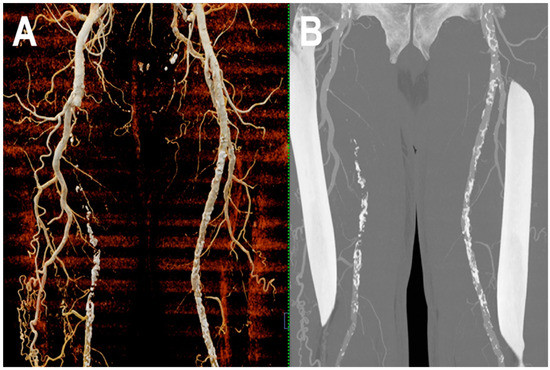

3.5. Peripheral Arterial Disease

- Shwaiki, O.; Rashwan, B.; Fink, M.A.; Kirksey, L.; Gadani, S.; Karuppasamy, K.; Melzig, C.; Thompson, D.; D’Amico, G.; Rengier, F.; et al. Lower extremity CT angiography in peripheral arterial disease: From the established approach to evolving technical developments. Int. J. Cardiovasc. Imaging 2021, 37, 3101–3114. [Google Scholar] [CrossRef] [PubMed]